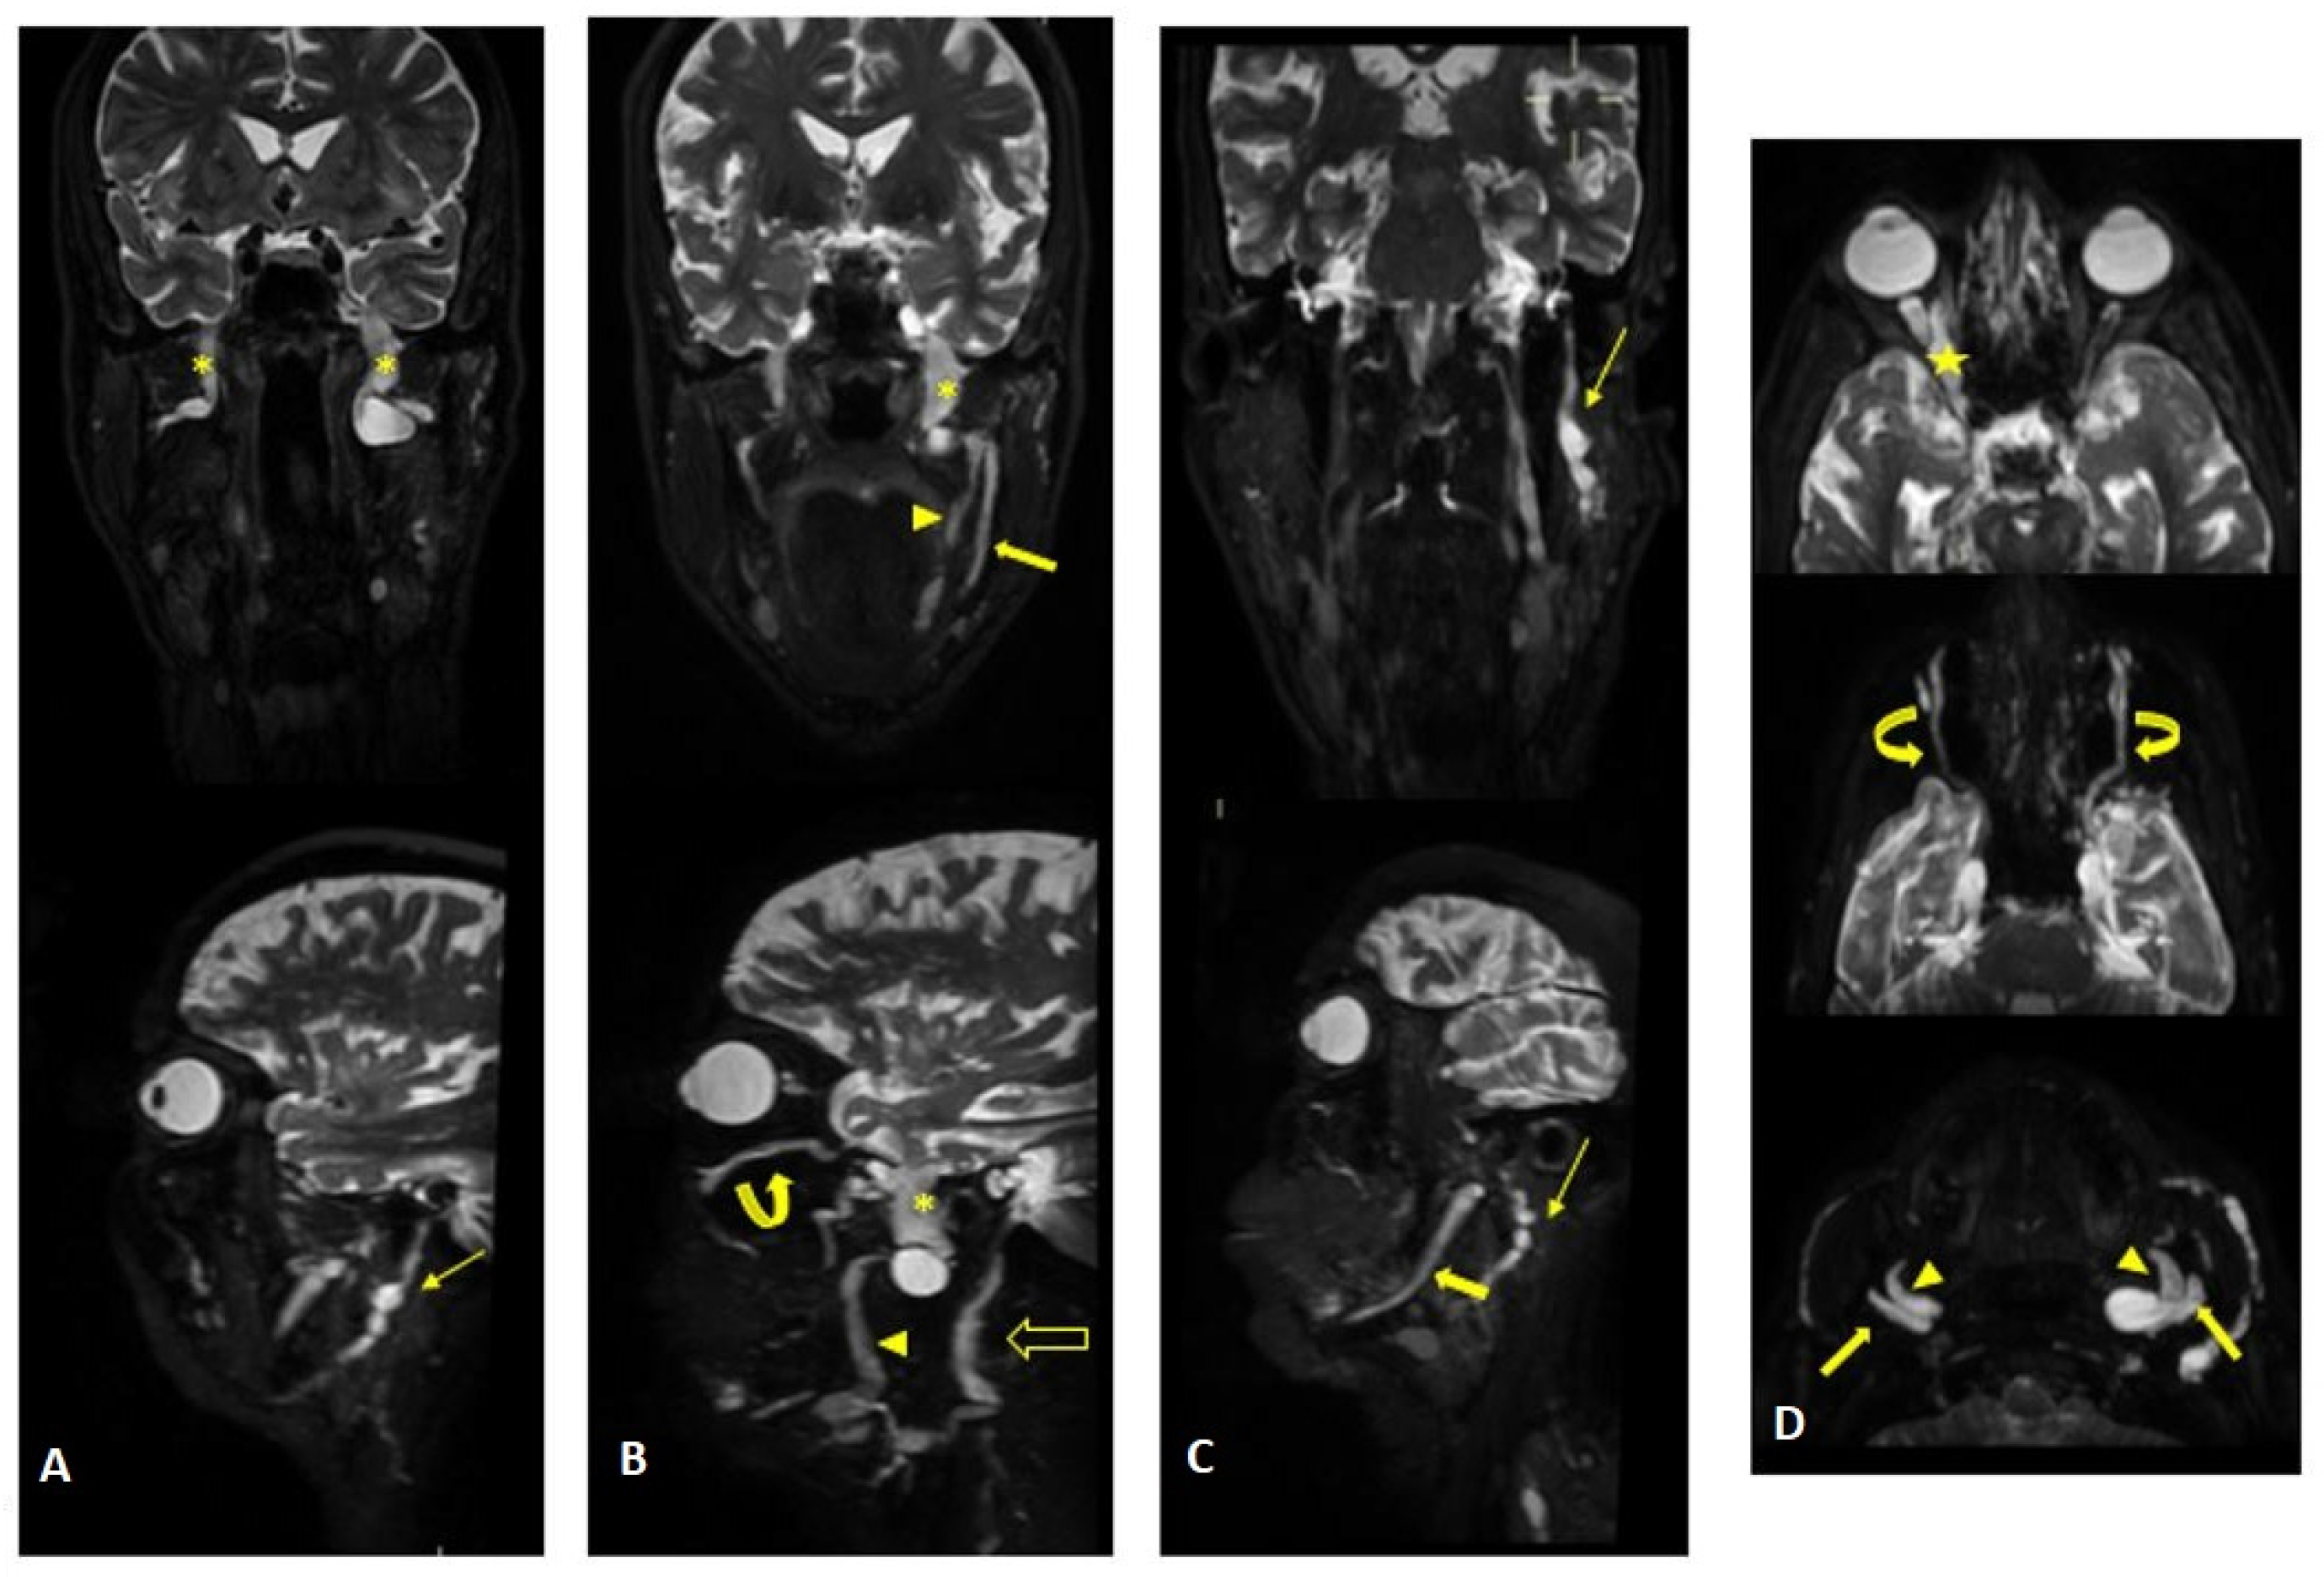

Figure 2.

MR (multiplanar reconstructions) of 3D cube neurography images show pathological, thickened cranial nerves along their extracranial course, with some cystic-like components. The images show the involvement of trigeminal branches V1 in ((D)—yellow star), V2 in ((B,D)—curved arrows with a transverse diameter after inferior orbital foramen: left 1.8 mm; right 2.6 mm) and V3 from its passage in the foramen ovale (asterisks in (A,B)) to its lingual (arrowheads in (B,D)) and alveolar divisions (thick arrows in (B–D)); the involvement of the left facial nerve in its intraparotid course (thin arrows in (A,C)) and the hypoglossal nerve (open arrow in (B), transverse diameter at C1 level: left 4.6 mm; right 2.1 mm).

MR findings: increase in thickness and signal intensity in T2 W images of lumbar and sacral roots, particularly in the left S1 root that appears to be pathological (Figure 8). Pathological alterations of the left sciatic nerve, characterized by a significant increase in volume with associated fascicular hypertrophy and an increase in signals in the T2w images, especially at the middle and lower thigh and extending in the leg to the tibial nerve. An increase in nerve thickness, a moderate signal increase on T2w images, and fascicular hypertrophy without evident alterations of the tibial nerve signal characterized initial and subtle alterations in the right sciatic nerve. Signs of acute and chronic muscle denervation in the left leg and thigh and initials in the right leg (Figure 9).

Figure 8.

MIP (Maximum Intensity Projection) reconstructions of the 3D cube nerve-MR sequence of the lumbosacral plexus documented a moderate and diffuse increase in thickness and signal intensity on T2W images of the lumbar and sacral roots; the left S1root (arrows) appears to be pathological (thickened and markedly hyperintense in T2w). Transverse diameter S1 roots (n.v. * 5.27 ± 0.53) left 8.4 mm; right 8.2 mm). * Normal values (n.v.) according to the recent study of Su X et al. [20].

Figure 9.

Pathological alterations of the left sciatic nerve (thin arrows in (B,D)), characterized by a significant increase in volume (CSA in the upper third of the thigh of about 123 mm2) with associated fascicular hypertrophy and an increase in signals in T2w images, especially in the height of the middle and lower third of the thigh and with extension to the tibial nerve (thin arrow in (F)), up to the lower third of the leg. Also, in the right sciatic nerve, there are some alterations (thin arrows in (B,D), much more tenuous than the contralateral nerve, characterized by an increase in the thickness of the nerve (CSA at the upper third of the thigh of about 110 mm2), a moderate increase signal in T2w images and fascicular hypertrophy, without evident tibial nerve signal alterations. Mixed denervation, acute and chronic, of left and right semimembranosus and posteromedial compartment muscles of the left leg (muscle hyperintensity and fascial edema in STIR, thick arrows in (D,F)) and fat replacement (muscle bundle atrophy with replacement of hyperintense tissue at T1W in (A,C,E), more evident in some areas: arrowheads in (C,E)).